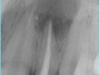

Al examen radiográfico, se observa una zona radiolúcida que ocupa todo el espacio de la cámara pulpar. Presencia de un sólo conducto recto a todo lo largo. Ensanchamiento del espacio del ligamento periodontal. Gran zona radiolúcida en el área periapical sugestiva de lesión periapical.

Diagnóstico: Necrosis Pulpar con lesión periapical.

El hidróxido de calcio (CaOH2) su uso fue introducido en 1920 por B.W. Hermann. Es un polvo blanco alcalino pH 12.8, poco soluble en agua. Indicado como medicación intraconducto, solución irrigadora, tratamiento de reabsorciones, cemento sellador, reparación de perforaciones, recubrimientos pulpares, apexificación y apexogenesis. Posee un alto poder antiséptico y antimicrobiano. Estimula condiciones favorables de reparación de los tejidos. Podemos observar una vez finalizado el tratamiento como toda esa zona radiolúcida se reparaba por la acción del CaOH2 en varias ocasiones y completado el proceso de reparación con el tratamiento de conducto en los controles radiográficos a distancia del tiempo. El diente permanece en boca; funcionalmente y sin presentar evidencias de signos y la paciente se encuentra asintomática.